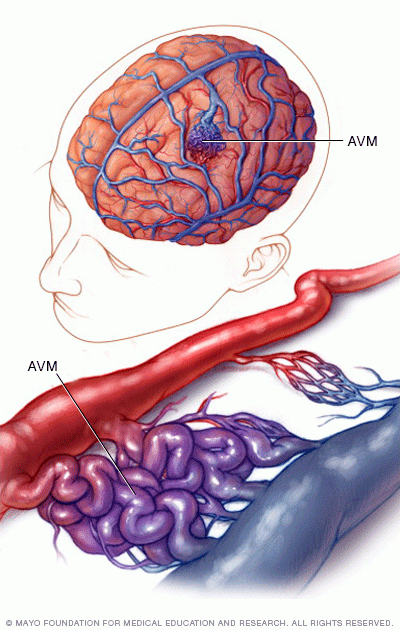

Intracerebral hemorrhage

A brain AVM may cause bleeding in the brain, known as a hemorrhage. Bleeding can damage the surrounding brain tissue. The CT scan on the left and the illustration on the right show an intracerebral hemorrhage.

Complications of a brain arteriovenous malformation (AVM) include:

• Bleeding in the brain. A brain AVM puts extreme pressure on the walls of the affected arteries and veins. The pressure causes the arteries and veins to become thin or weak. This may result in the AVM breaking open and bleeding into the brain, known as a hemorrhage.

This risk of a brain AVM bleeding ranges from around 2% to 3% each year. The risk of bleeding may be higher for certain types of AVM. Risk also may be higher in people who have had a brain AVM bleed in the past.

Some hemorrhages associated with brain AVMs aren't detected because they cause no major symptoms. However, potentially dangerous bleeding can occur.

Brain AVMs account for about 2% of all hemorrhagic strokes each year. In children and young adults who experience brain hemorrhage, brain AVMs are often the cause.